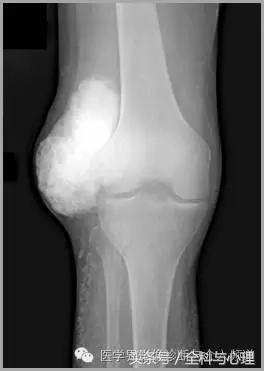

五、滑膜软骨瘤病

1°少见,病灶数量多,大小均匀,相邻关节正常。

2°多见,病灶数量少,大小不一,多伴有退行性骨关节病。

软组织钙化与骨化,软组织钙化和骨质增生 滑膜骨软骨瘤病 1°

软组织钙化与骨化,软组织钙化和骨质增生 滑膜骨软骨瘤病 2°

软组织钙化与骨化,软组织钙化和骨质增生 滑膜骨软骨瘤病